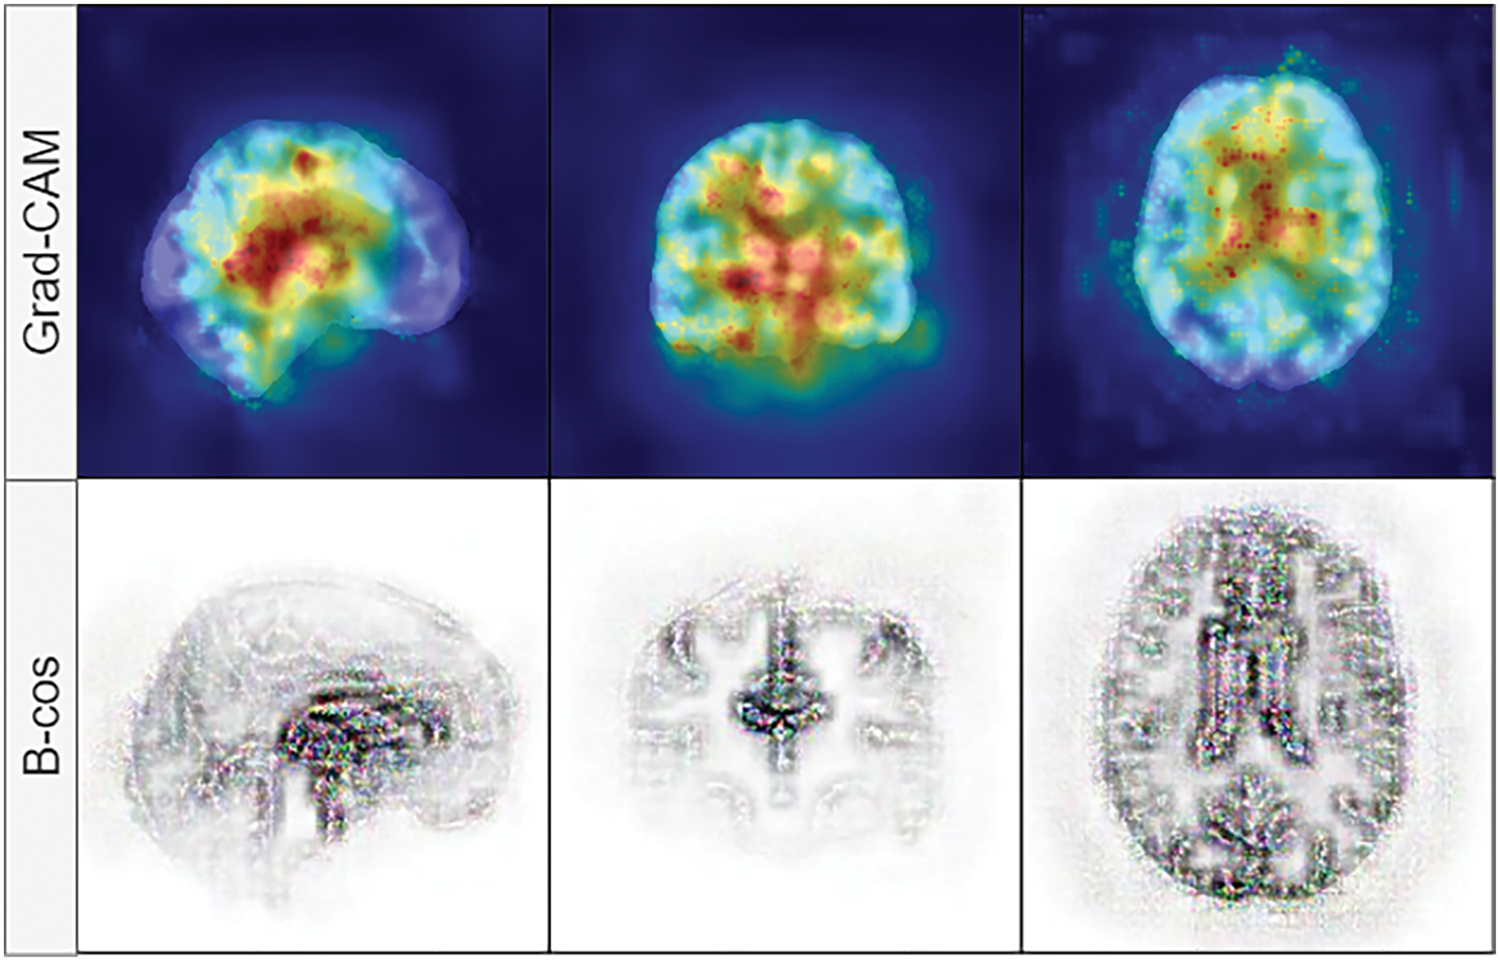

We have replaced the original convolution and batch normalization layers with the B-cos modules described in [44]. The convolution modules (Conv2D) and batch normalization (UncenteredBatchNorm2D) of the B-cos networks allow the visualization of the highest contributing features during inference. They work similarly to Grad-CAM [49] or, in the case of numerical features, SHAP values [50]. We chose B-cos modules over Grad-CAM because of several reasons: faithfulness, with B-cos networks replacement of layers in models, is necessary, and these layers capture summaries of all computations during training; they also capture both positive and negative contributions, which leads to more detailed and focused explanations, where Grad-CAM is a post-hoc computation and it may not be faithful to the network’s internal computations; high quality, clearly focused contributions, Grad-CAM captures saliency maps of gradients backpropagated through the network and only highlights the regions in the images, that contribute most to the prediction, but usually are coarse and noisy, where B-cos provides focused and clear contribution maps, that are easier to interpret. An example of Grad-CAM vs. B-cos feature contribution maps is shown in Fig. 2.

Figure 2: Visual comparison between Grad-CAM (top row) and B-cos (bottom row) feature contribution maps. B-cos explanations are more focused, where Grad-CAM provides a high-level overview of the region that contributes the most in classification